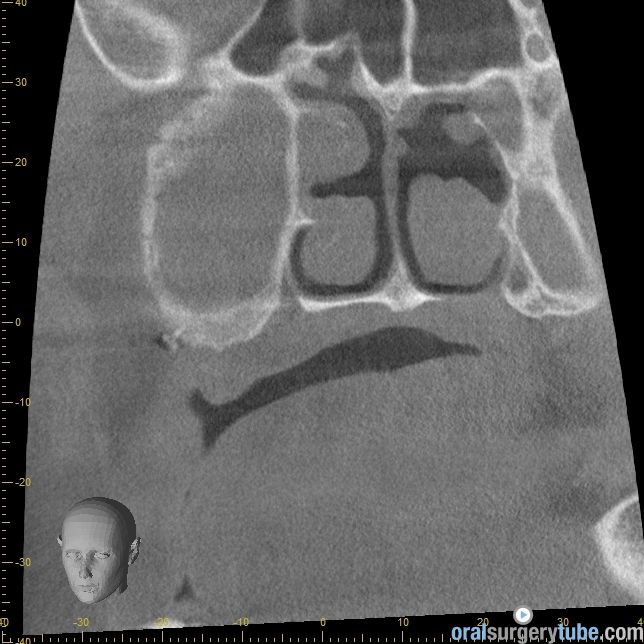

Cierre de comunicación orosinusal con tejido duro y blando